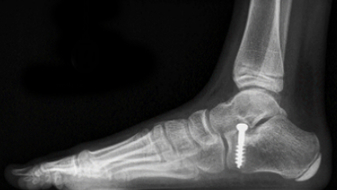

Juli's Fuss-OP

Oktober 2018, der Knochen muss gerichtet werden.